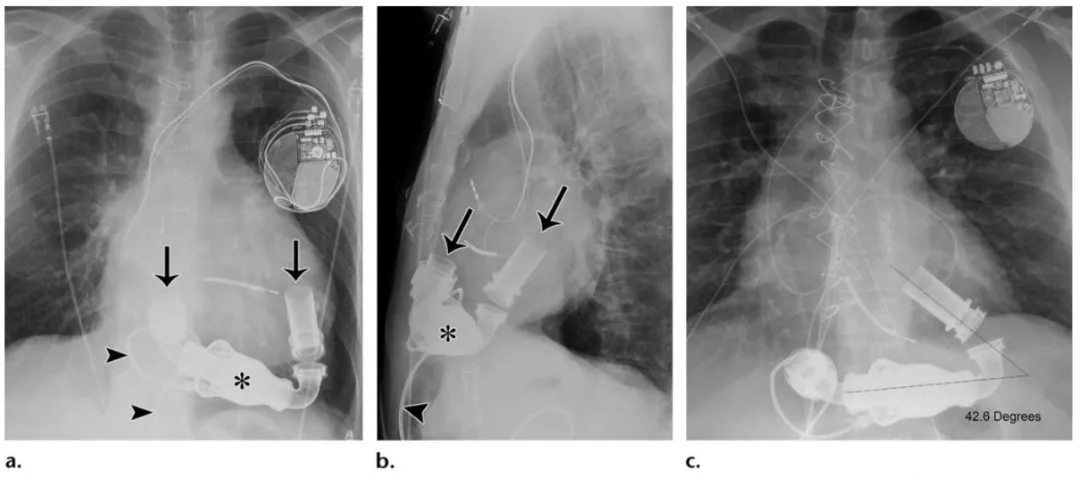

胸部治疗和监护设备的x线表现大全

图片尺寸1080x479